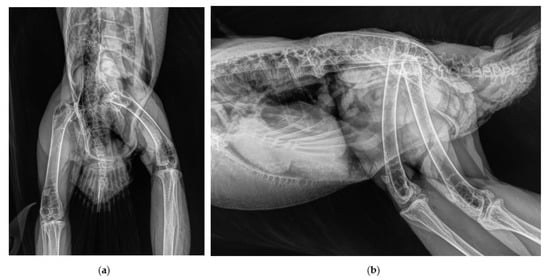

2.2. Surgical Procedure and Post-Surgery Management